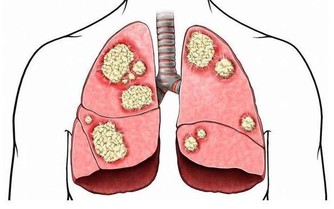

國外科學家研究發現,鎂可激活325個酶系統,把鎂稱為“生命活動的激活劑”是當之無愧的,而且,鎂對人的心臟血管具有重要的保護作用,人體如果缺鎂,就會導致心跳過速、心律不齊以及心肌壞死和鈣化等種種健康問題。